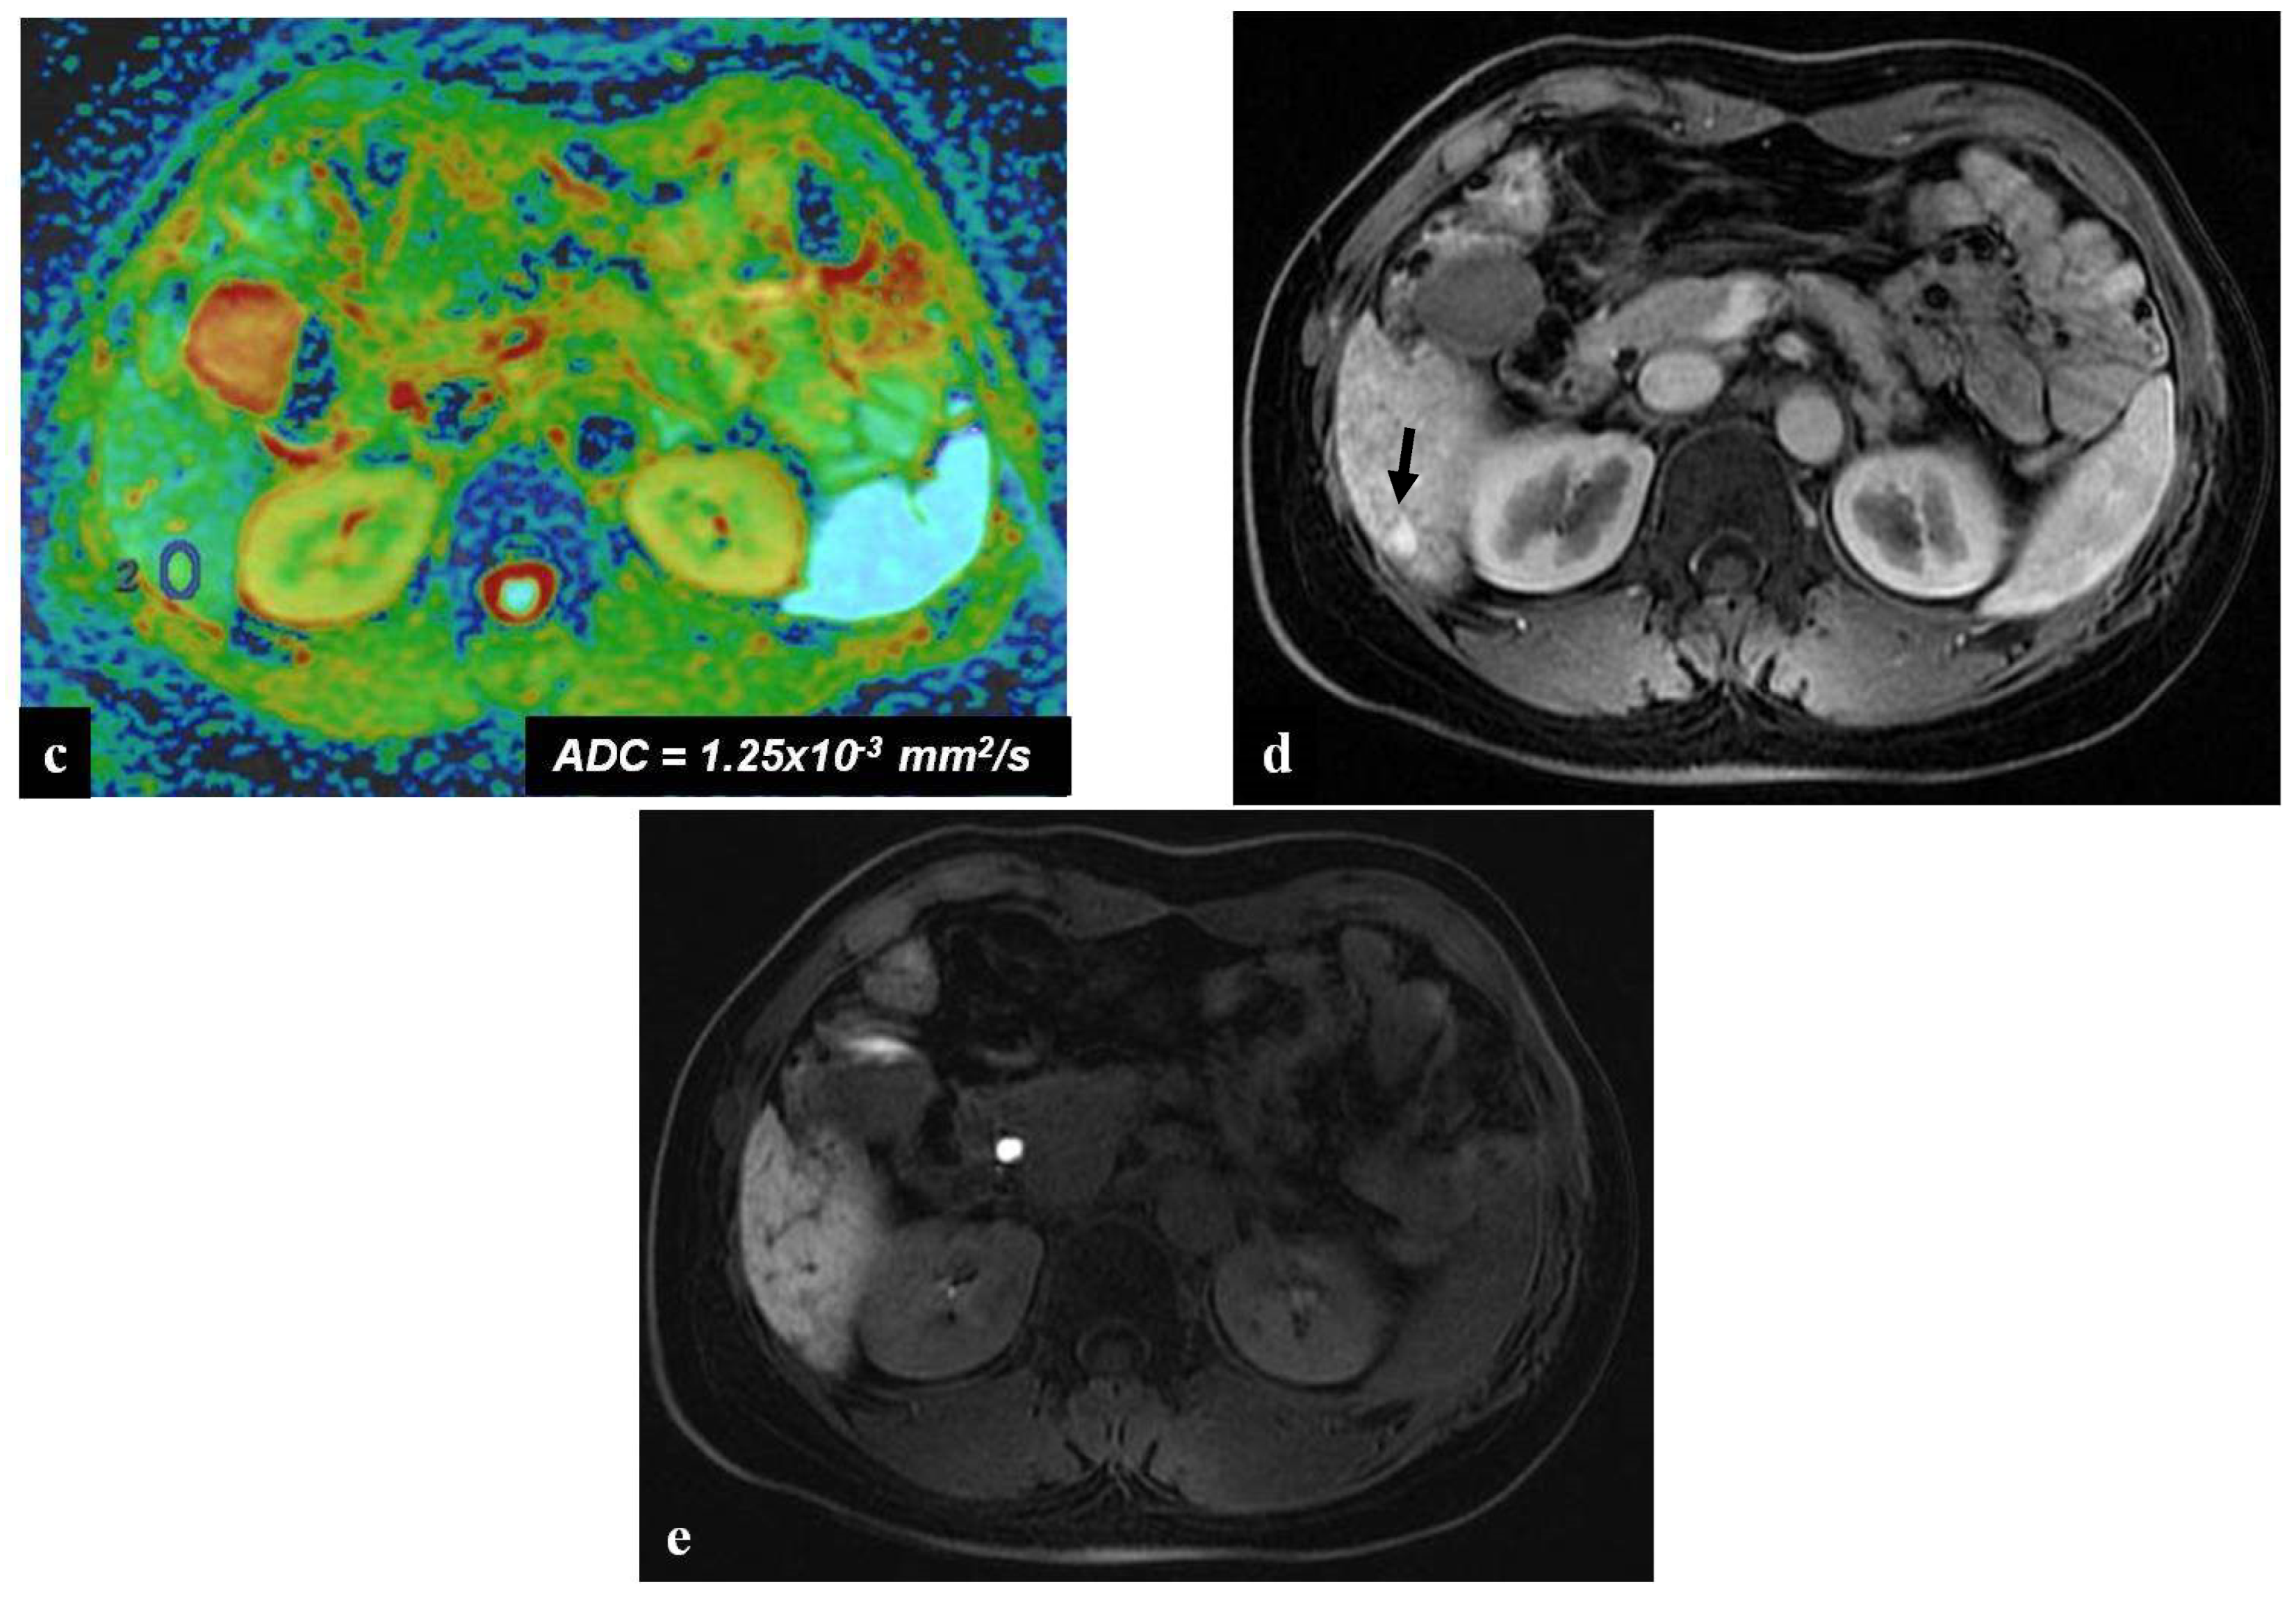

Figure 4.

(a–e) A 62-year-old woman with hepatic metastases from rectal cancer undergoing neo-adjuvant chemotherapy with folinic acid, 5-fluorouracil, and oxaliplatin (FOLFOX). After chemotherapy, a new centimetric lesion appeared in segment 6 (arrow). The lesion was not appreciable on the T2-weighted image (a) and on the DW-MRI image, with b-values of 1000 s/mm2 (b) and an ADC value = 1.25 × 10−3 mm2/s in the reconstructed ADC map (c). After the administration of Gd-EOB-DTPA, a lesion with strong central enhancement and hypointense periphery was identified in the arterial phase image (d) but was no longer recognizable in the hepatobiliary phase image (e). The findings are consistent with a pseudotumor lesion. In the hepatobiliary phase image (e), diffuse hepatic reticular hypointensity of the surrounding liver parenchyma is also appreciably suggestive of SOS.

A radiologist should be aware that sometimes oxaliplatin-induced SOS may manifest as new focal liver lesion, also known as focal chemotherapy-induced hepatopathy [38], mimicking liver metastasis and constituting a new challenge [38,40]. This is a comprehensive concept that includes several pathologic conditions such as pseudotumor, peliosis, and nodular regenerative hyperplasia [6]. According to Han et al. [38], focal chemotherapy-induced hepatopathy on gadoxetic acid-enhanced MRI shows no rim-enhancement during the arterial and portal phases, intermingled hypointensity and ill-defined margins during the HB phase, and a lack of diffusion restriction on DW-MRI [4,38].

Sometimes in the setting of SOS, a hepatic pseudotumor, characterized pathologically by sinusoidal dilatation and congestion of the hepatocytes with inflammatory cellular infiltration and areas of fibrosis, may arise [41]. On MRI, a pseudotumor of SOS must be suspected in the case of an irregular lesion with peritumoral enhancement and central low attenuation or signal intensity [21]. As a pseudotumor of SOS may simulate focal nodular hyperplasia, atypical HCC, or liver metastasis, DW-MRI is recommended for improving differential diagnostic efficiency between a pseudotumor of SOS and malignancy [38,41] (Figure 4). In fact, while the metastases are hyperintense in DW-MRI images at high b-values and have much lower ADC values than normal hepatic parenchyma, a hepatic pseudotumor appears isointense at high b-values and has ADC values higher than the metastases but lower to those of benign liver lesions. This can be explained by the increased physical barrier and decreased perfusion, as suggested by Zhang et al. [12] in patients with diffuse liver injury from chemotherapy.